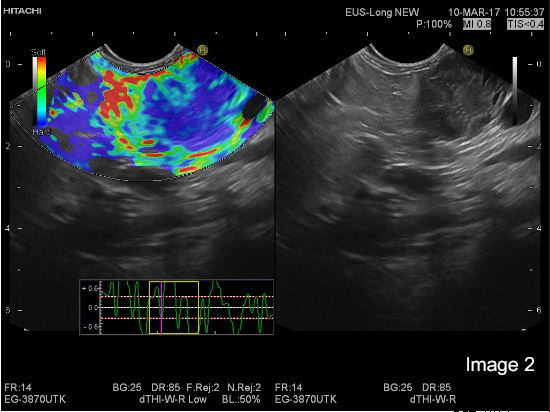

EUS was performed with a Pentax E-3870 UTK linear echoendoscope and Hitachi Ascendus scanner. On B-mode EUS the tumour in the head and tail appeared very similar with a generally hypoechoic inhomogeneous echogenicity pattern and apparently small cystic areas within otherwise solid tumours. Also, the two smaller lesions could be identified in the body and tail of the pancreas. We concentrated the further examination on the lesion in the tail of the pancreas, with a diameter of 25 mm (Image 1 and 2).

On strain based elastography, the tumour tissue was repeatedly imaged as harder than the surrounding pancreatic parenchyma (Image 1 and 2).

Image 2: The hypoechoic tumor tissue in the B mode image is repeatedly corresponding to the blue area indicating harder tissue in the elastogram (left)